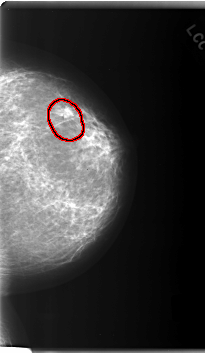

FILE: C_0165_1.LEFT_CC.OVERLAY

TOTAL_ABNORMALITIES 1

ABNORMALITY 1

LESION_TYPE MASS SHAPE ROUND MARGINS SPICULATED

ASSESSMENT 5

SUBTLETY 5

PATHOLOGY MALIGNANT

TOTAL_OUTLINES 1

BOUNDARY